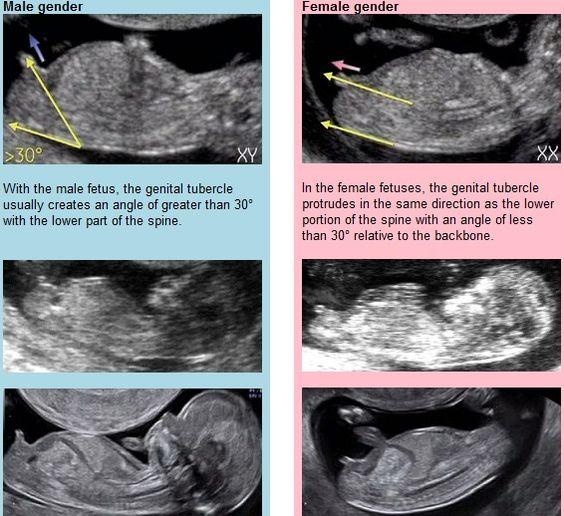

@2hanah Je tam vidět jen pohlavní hrbolek 🙂. Pohlavi se určuje podle jeho sklonu. Když směřuje nahoru, tak kluk, když rovnoběžně se zakřivením páteře, tak holka. Na velký ultrazvuk jdu az za 2 týdny 🙂. Ovšem zatím většina tipovala holcicku... Sama jsem zvědavá, co to je... Na druhou stranu přemýšlím, jestli si nenechat překvapeni do porodu 🙂